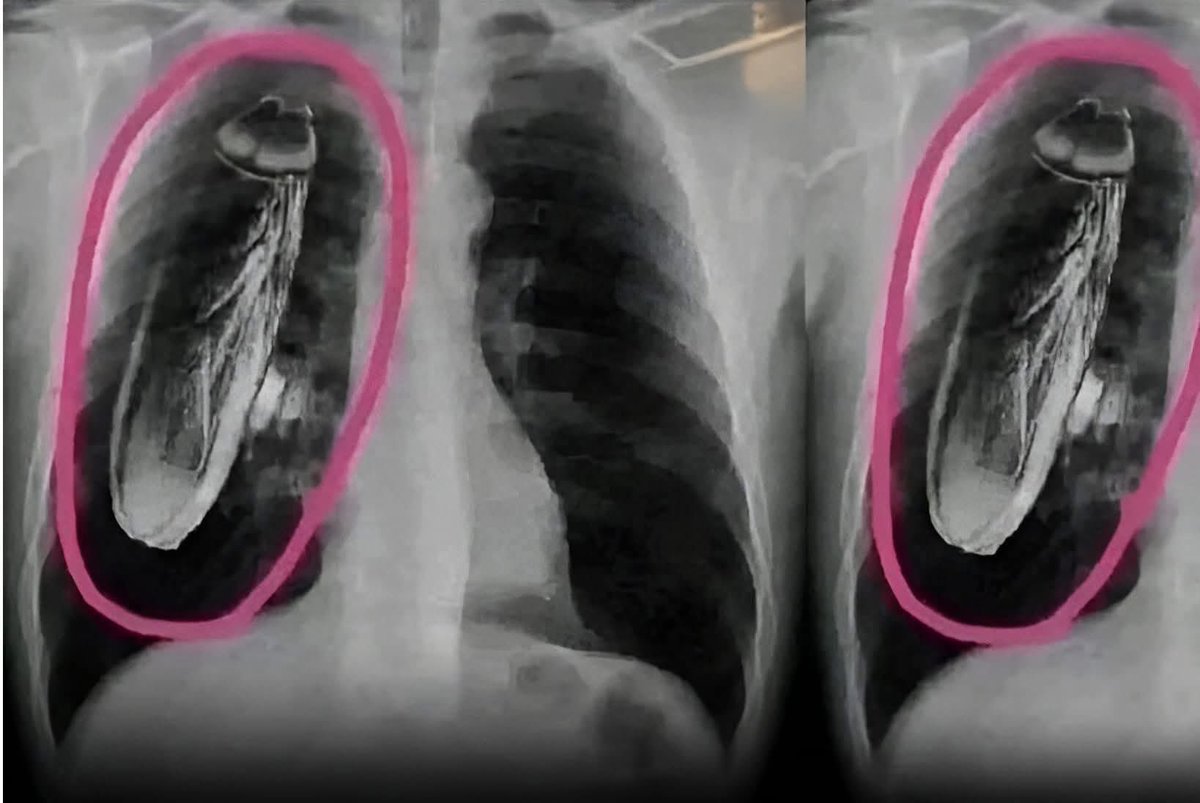

title तैमूर का जीजा 😎 🇮🇳 - हिमाचल प्रदेश के नालागढ़ जिले में एक स्थान है "बद्दी" बद्दी में आए आज सिंगापुर के एक पर्यटक को सीने में दर्द महसूस हुआ और इलाज के लिए वहां सरकारी अस्पताल गया | डॉक्टर ने अपने कुछ टेस्ट पर एक्स-रे किया और कहा कि तुरंत सिंगापुर वापस इलाज के लिए चले जाओ क्योंकि उसके सीने https://t.co/SKalQZFdUL

content हिमाचल प्रदेश के नालागढ़ जिले में एक स्थान है "बद्दी" बद्दी में आए आज सिंगापुर के एक पर्यटक को सीने में दर्द महसूस हुआ और इलाज के लिए वहां सरकारी अस्पताल गया | डॉक्टर ने अपने कुछ टेस्ट पर एक्स-रे किया और कहा कि तुरंत सिंगापुर वापस इलाज के लिए चले जाओ क्योंकि उसके सीने https://t.co/SKalQZFdUL